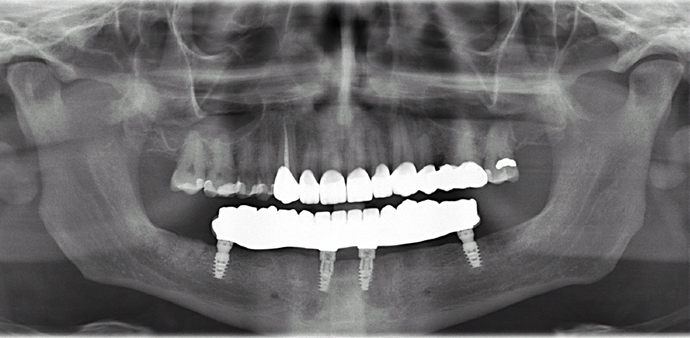

All-on-4/ Full Mouth Dental Implants / Teeth in a Day: Case 18- Upper crowns and Lower All-on-4 Bridge

This patient, a mental health counselor was frustrated that despite taking care of his teeth all his life, he ended up having several cavities that made him lose several of his lower teeth. His cavities in his upper natural teeth was manageable through crowns and his remaining lower teeth were extracted and new implants and teeth were installed in one day without the need for any bone grafting.

Procedures : extractions, implants, All on 4 , Teeth in a day, no bone grafting and full mouth reconstruction with monolithic zirconia bridges.